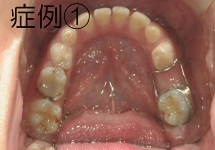

クワドヘリックス(QH)

上顎骨の横幅を広げる効果があり、上顎の幅が狭い時や、歯の生えるスペースが足りない時に使用します。症例2の場合、内側に入っていた左上2番が、装置に押し出されて正常な位置に移動しました。